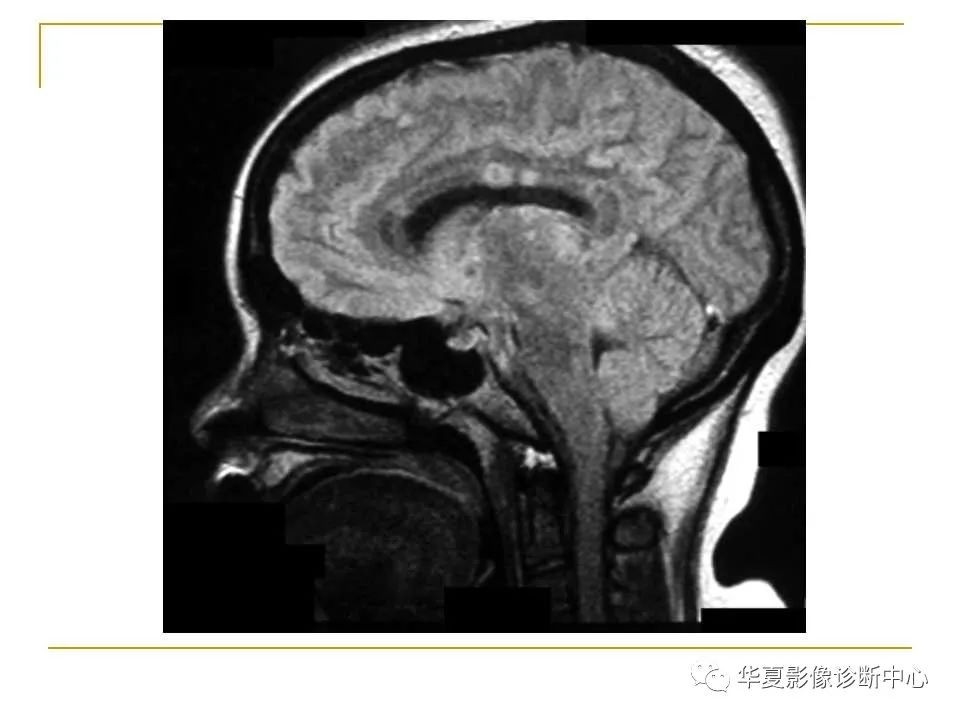

胼胝体解剖及病变大全